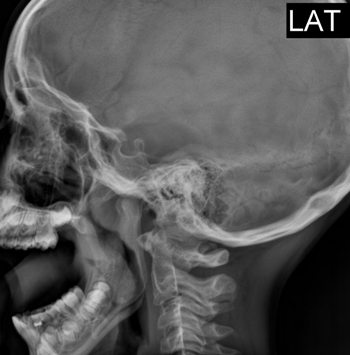

В рентгенологический кабинет клиники №1 Витерра Беляево по направлению от оториноларинголога (ЛОР) поступил ребенок 2010 г.р. с жалобами на постоянную заложенность носа, кашель, нарушение носового дыхания, выделения из носа, храп во сне.

В течение 2-х лет лечится консервативно - без улучшения состояния.

Пациенту выполнено рентгенологическое исследование области носоглотки в боковой проекциии (с открытым ртом), при котором выявлено:

Практически полное перекрытие до 3/3 воздушного столба за счет сферической тени неправильной формы, исходящей из дорсальной (задней стенки).

Данная рентгенологическая картина - гипертрофии аденоидных вегетаций III-й степени, клинически соответствует обострению хронического аденоидита, осложненного катаральными, средними отитами.

Пациенту рекомендовано продолжить лечение у оториноларинголога с дальнейшей эндоскопической аденотомией в плановом порядке.